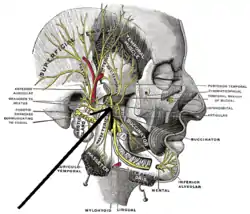

Mandibular division of the trigeminus nerve. (Internal pterygoid nerve visible but not labeled.) | |

Mandibular division of trifacial nerve, seen from the middle line. Nerve to medial pterygoid labeled at bottom. | |